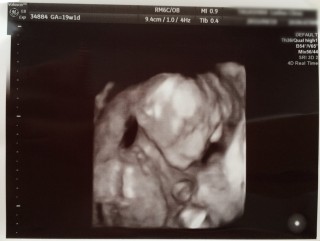

この日の健診で性別が男の子だとわかりました! こうやって私のお腹の中ですやすやと眠ってるんだぁと、 とても癒されました。 ぼくちゃんに早く会いたいです(*^^*)

初めて4Dでのエコー検診‼︎

お顔は見えなかったけど、手足を元気に

動かしてたのを見れて嬉しかった♡

性別は確定出来なかったけど、

現段階では60%女の子かなとの事^_^

次回の検診が待ち遠しい(ॢꈍ૩ꈍ)ॢ